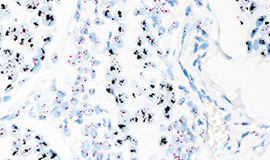

ベンタナ DISH HER2 トレーニングプログラムベンタナ DISH HER2を用いたDISH法の判定について学んでいただけます。